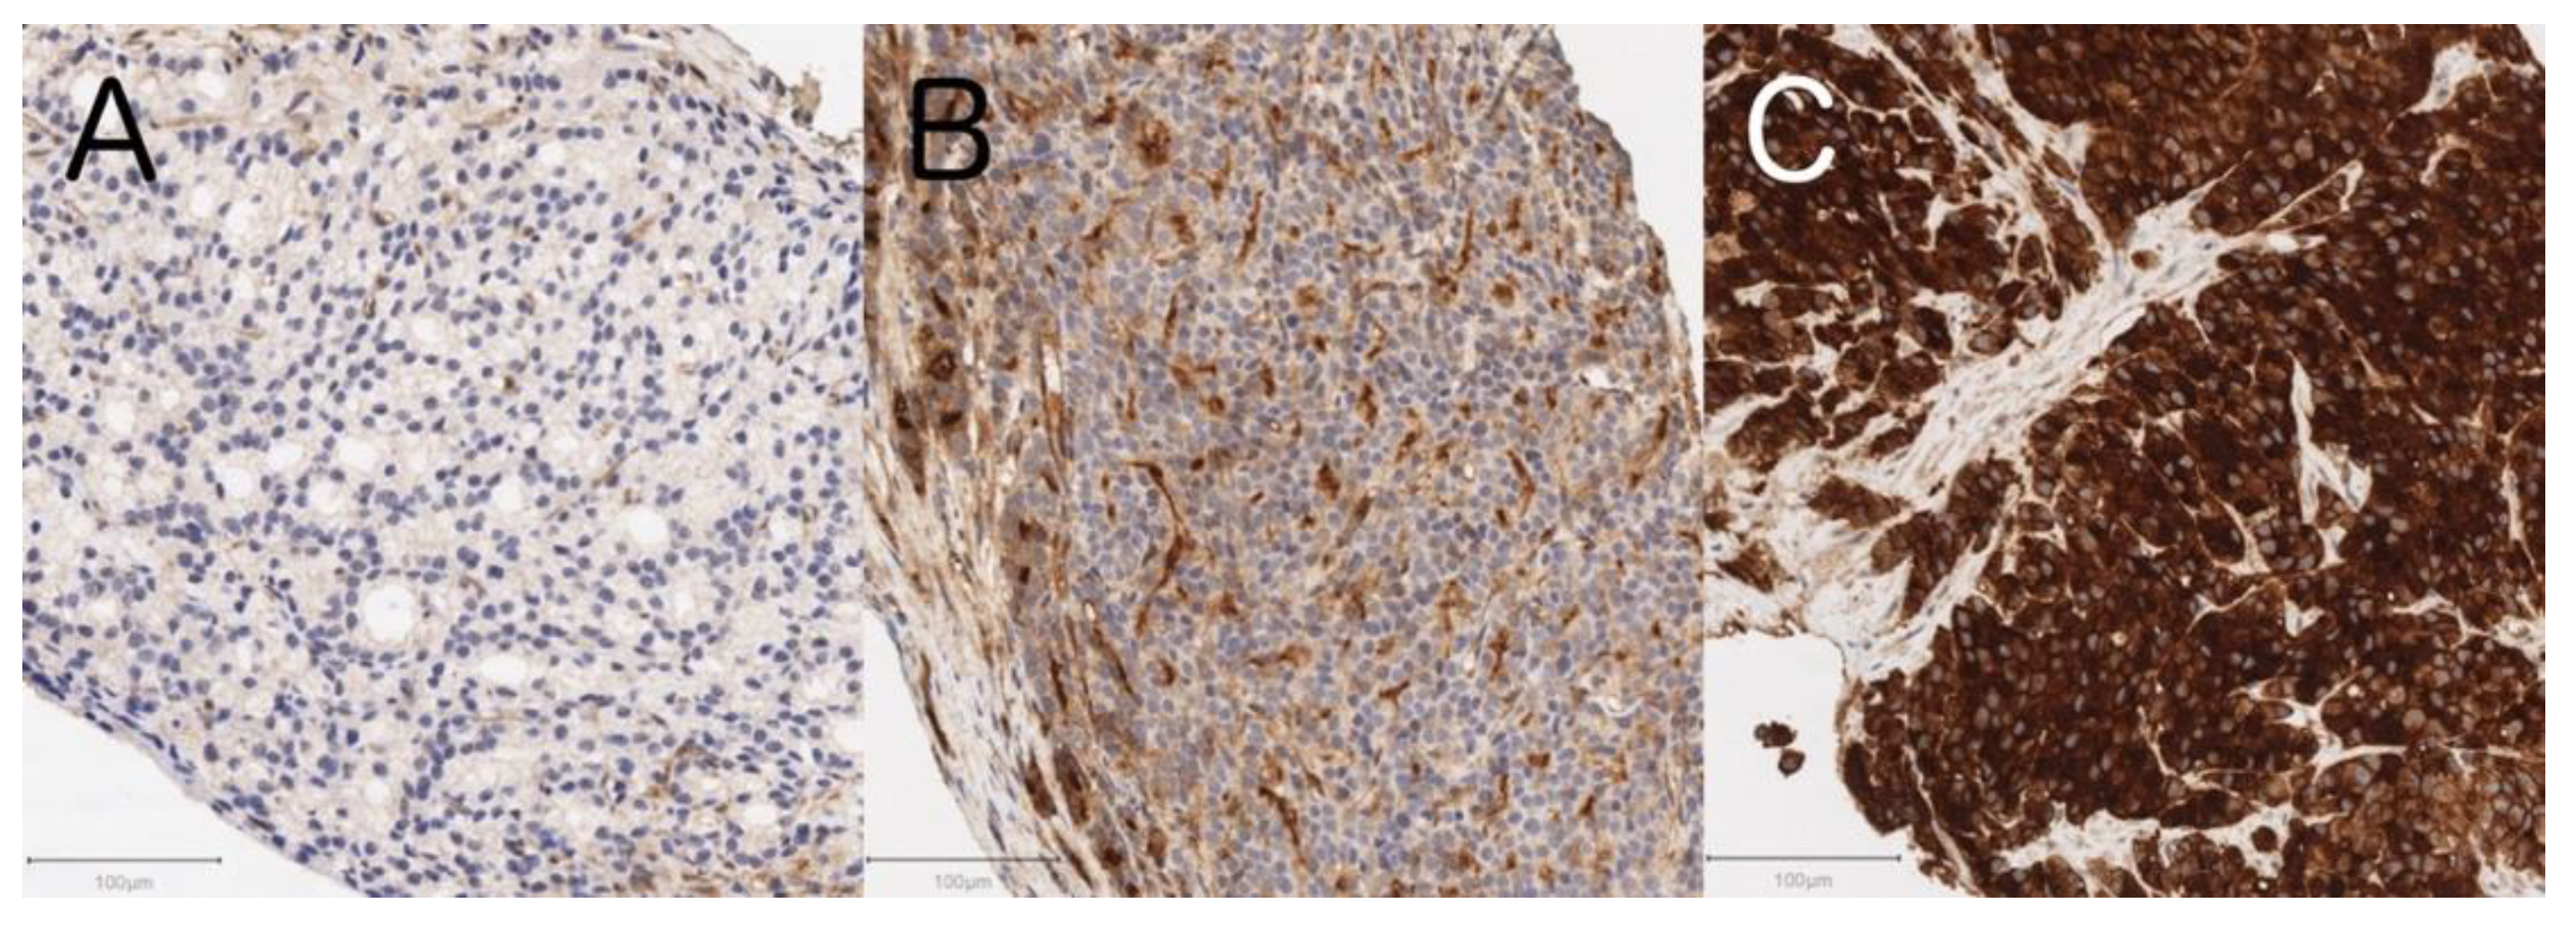

3.5. Tissue GGT Expression Status and Clinicopathological Characteristics including Serum GGT Levels in 29 De Novo mCSPC Men

| Characteristic at Diagnosis | Tissue GGT Expression Status | p | |||||

|---|---|---|---|---|---|---|---|

| Negative to Weak (n = 6) | Moderate (n = 12) | Strong (n = 11) | |||||

| Age [years], median (IQR) | 76.2 | (65.2–79.6) | 69.6 | (67.0–72.4) | 70.5 | (64.6–78.2) | 0.438 * |

| Gleason score, median (IQR) | 9 | (9–9) | 9 | (9–9) | 9 | (9–9) | 0.772 * |

| Metastatic sites | 0.492 † | ||||||

| Lymph node only (M1a) | 0 | (0%) | 0 | (0%) | 0 | (0%) | |

| Bone/bone + lymph node (M1b) | 5 | (83%) | 9 | (82%) | 10 | (100%) | |

| Any visceral (M1c) | 1 | (17%) | 2 | (18%) | 0 | (0%) | |

| Serum GGT [U/L], median (IQR) | 15 | (10.5–33.3) | 33 | (23.5–53.3) | 64 | (50–74) | 0.018 * |